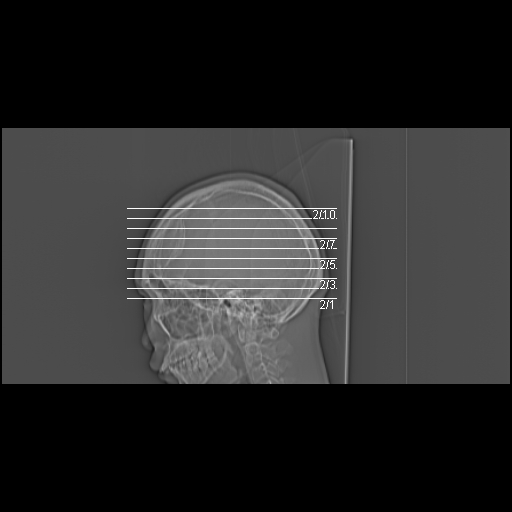

标题: CT21939:男20岁,外伤一年后,现头疼. [打印本页]

标题: CT21939:男20岁,外伤一年后,现头疼.

左侧额部硬膜外血肿机化、骨化。

左侧额部硬膜外血肿机化、骨化